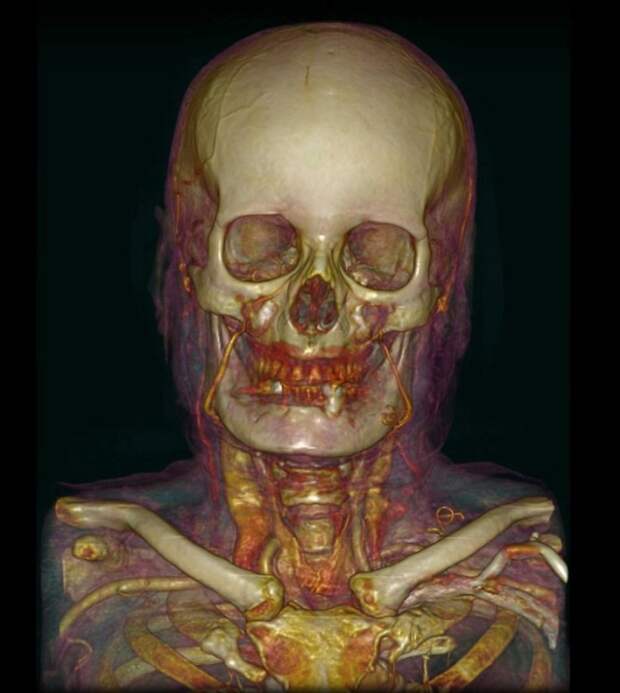

13. Томография сосудов и черепа